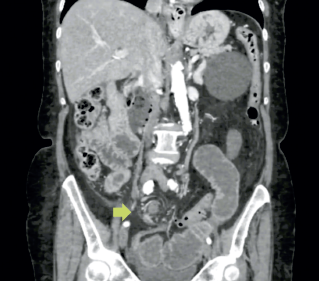

Se solicitó tomografía abdominal con medio de contraste IV, la cual mostró imagen en remolino a nivel de mesogastrio sugestiva de hernia interna; apéndice cecal de 0.8 mm con presencia de aire en su interior; distensión de asas intestinales, colon colapsado y divertículos en sigmoides sin datos de agudización (figura 1).

Imágenes: Salinas-García et al.

Figura 1 Corte coronal de tomografía abdominal (flecha) muestra el signo de remolino.